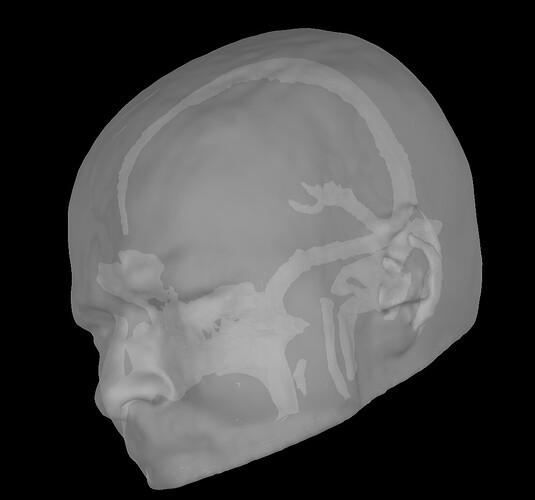

which does not really seem right. I have tried plotting in Matlab directly, suspecting a display issue, but, while if I plot the compact surface within the FEM (by exporting it in Matlab and selecting only the tissue labelled as compact), I get the right skull-like structure:

when I then scatter the vertices of the brainstorm extracted surface, I get again: